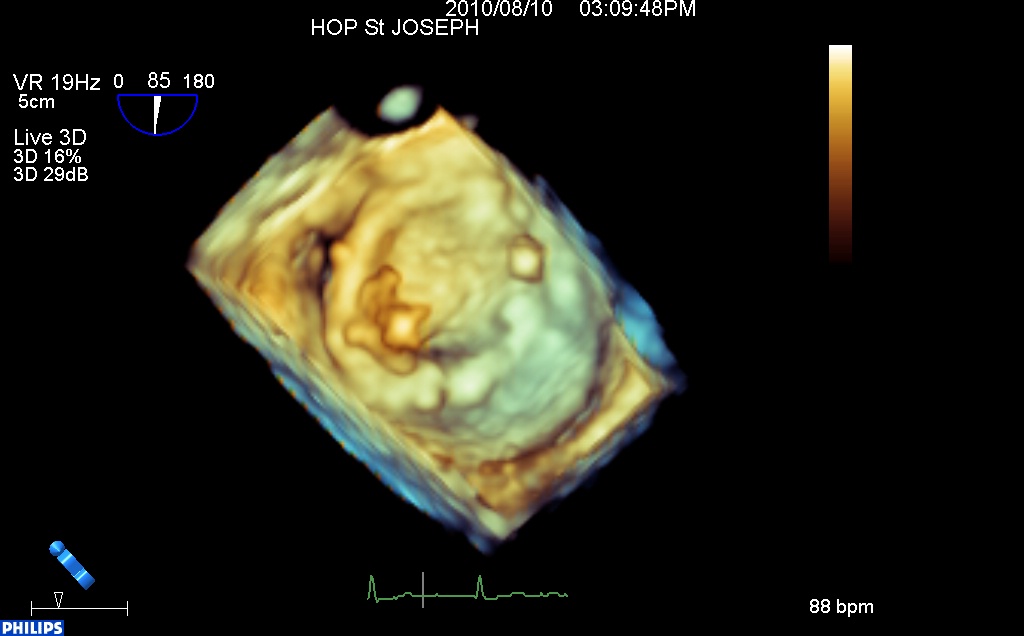

thrombose non obstructive de prothèse mitrale 3d from fish Nip echocardiographie on Vimeo.

En 3d, (l’aorte en haut, l’auricule à gauche), on retrouve coté commissure antérieure un thrombus mobile enchâssé dans la charnière de gauche, ne gênant pas (encore?) le mouvement des ailettes…